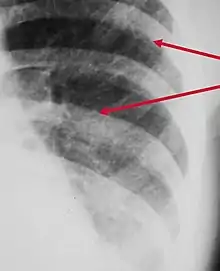

Peribronchial cuffing, also referred to as peribronchial thickening or bronchial wall thickening, is a radiologic sign which occurs when excess fluid or mucus buildup in the small airway passages of the lung causes localized patches of atelectasis (lung collapse).[1] This causes the area around the bronchus to appear more prominent on an X-ray. It has also been described as donut sign, considering the edge is thicker, and the center contains air.